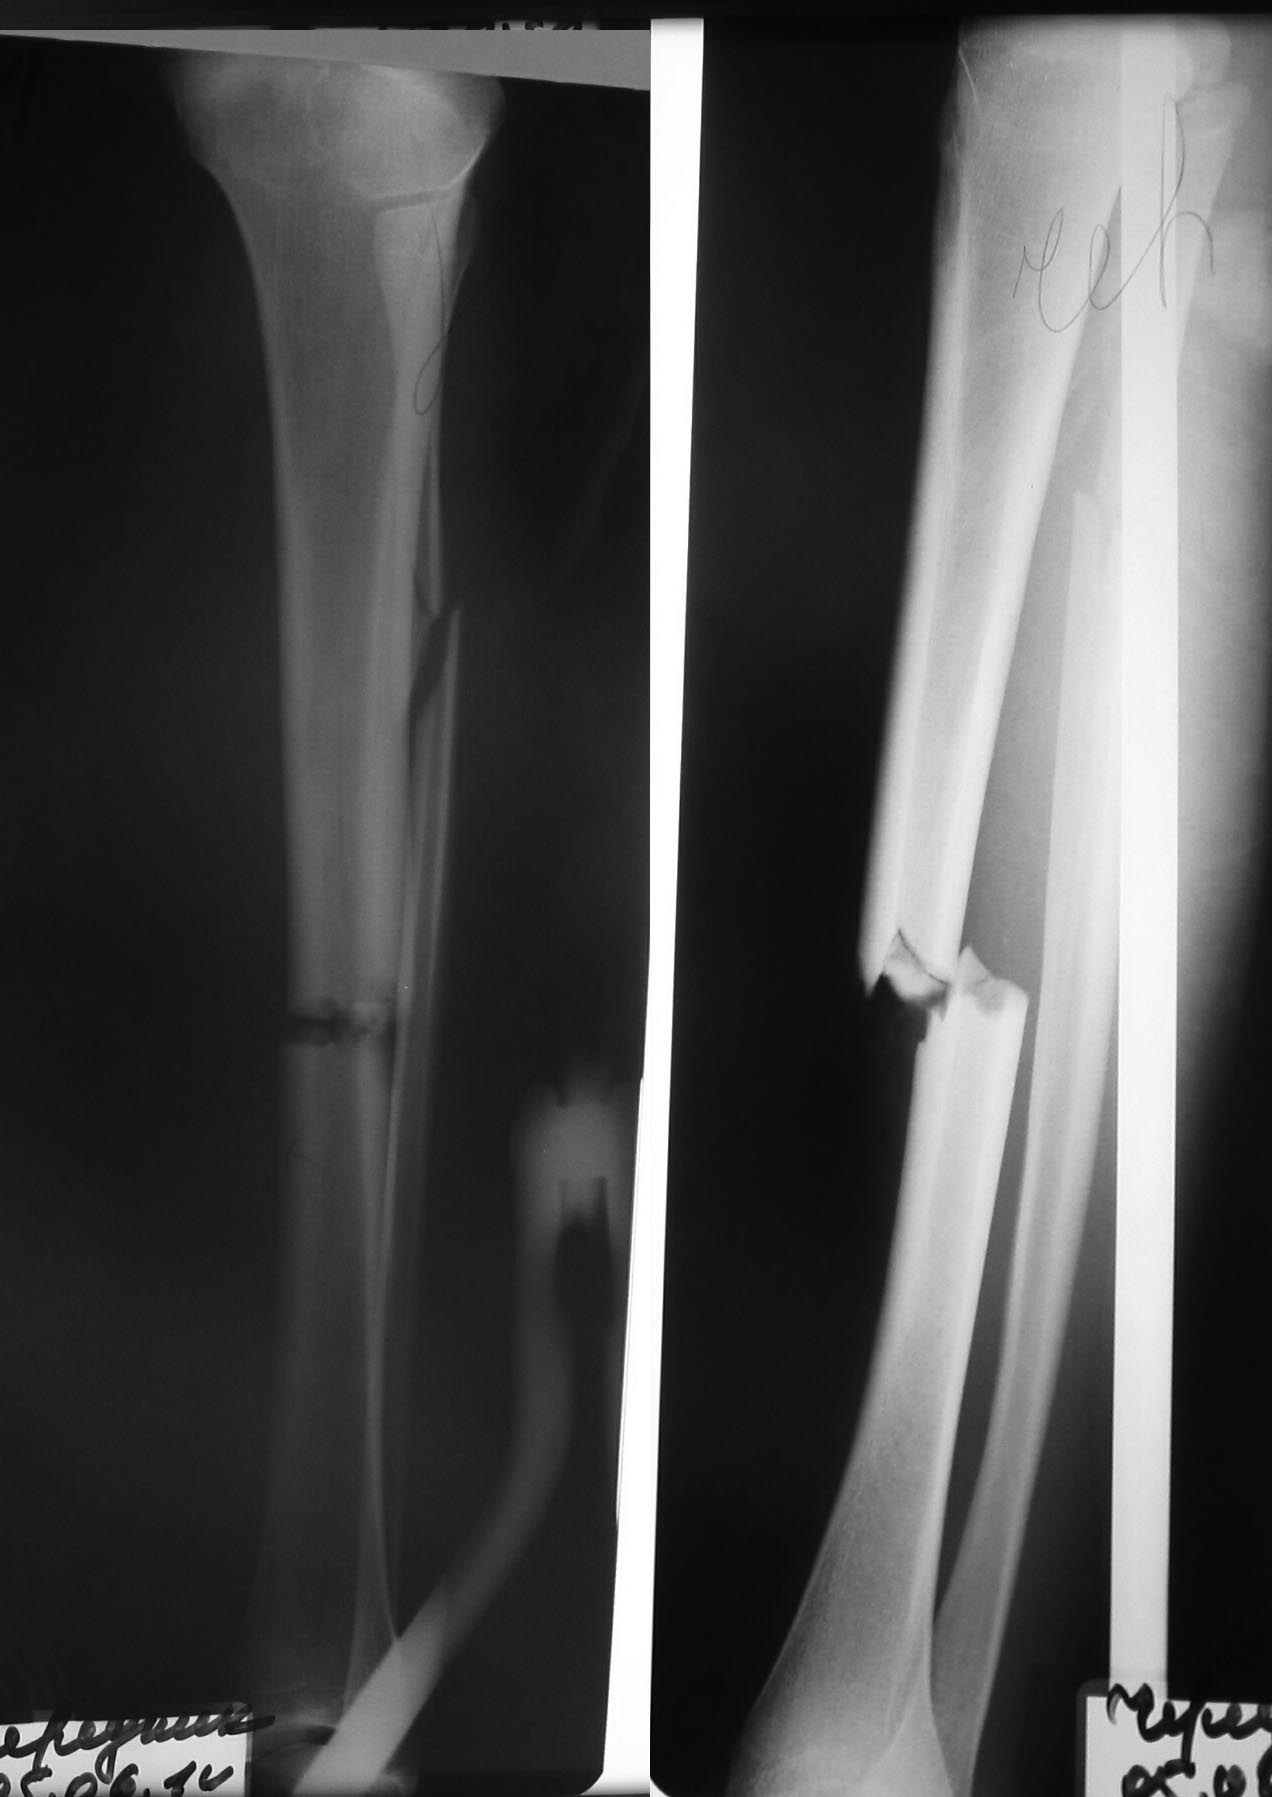

Травма в ДТП. Девочка. Перелом обеих костей голени практически тип 42-А3. Раны голени почти зажили, под корочкой. Для взрослого без сомнения использовал бы штифт. Что лучше для ребенка 14 лет, девочки, уважаемые коллеги?

Травма в ДТП. Девочка. Перелом обеих костей голени практически тип 42-А3.

Это поперечный?

1.покажите снимки. Невозможно дать совет не видя снимков

2. Если зона роста ещё открыта штифт делать нельзя - в будущем будет genu recurvatum

Ребёнок старшего возраста. Физарные пластинки почти исчезли. Всё правильно задумано. Если всё хорошо получилось - Проблем не будет точно.

Уважаемые господа, не выдержал! О чем вы? Перелом не репонирован!!!!!! И причины могут быть только две - или травматолог не обладает необходимыми навыками репозиции! Или есть интерпозиция мягких тканей!!!! В обеих случаях действия известны!!!!

В лечении переломов педиатрического возраста значение имеет возраст, рост и состояние зоны роста. Зона роста закрывается в среднем у девочек от 12-14 и у мальчиков от 14-16 лет.

Здесь поперечно-стабильный перелом, и несмотря на то, что возраст позволяет установить штифт, лучше под ЭОП сделать одномоментную срочную репозицию. Гипс с последующим брейсом по Сармиенто - не оставляет косметический дефект! При необходимости скелетного вытяжения, тогда надо закончить репозицию в первые часы, иначе нерепонированный перелом долго обуславливает отек проблемы с мягкими тканями.

Небольшие раны 1-3 см являются первой степенью открытых переломов и при таких переломах (I и II ст) после I&D, без риска осложнения, можно делать остеосинтез обычным или эластичным штифтом! Эластичные штифты имеют свои ограничения, и вес больного не больше чем 48-50 кг. Это вес, который выдерживают гибкие гвозди!